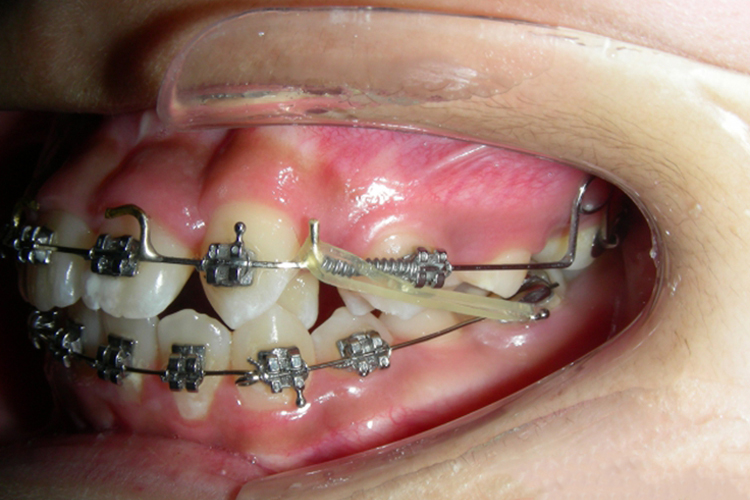

J形钩是应用口外的力量,结合头帽有效压低前牙,且支抗力稳固,但仅可晚间使用,白天无法使用。